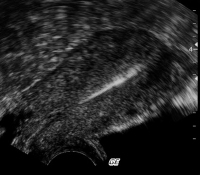

"Selten, aber typisch": Die extrauterine Dislokation des IUD - eine Übersicht

Journal für Gynäkologische Endokrinologie 2012; 6 (2) (Ausgabe für Österreich): 12-17 Journal für Gynäkologische Endokrinologie 2012; 6 (2) (Ausgabe für Schweiz): 14-19 Volltext (PDF) Summary Praxisrelevanz Abbildungen